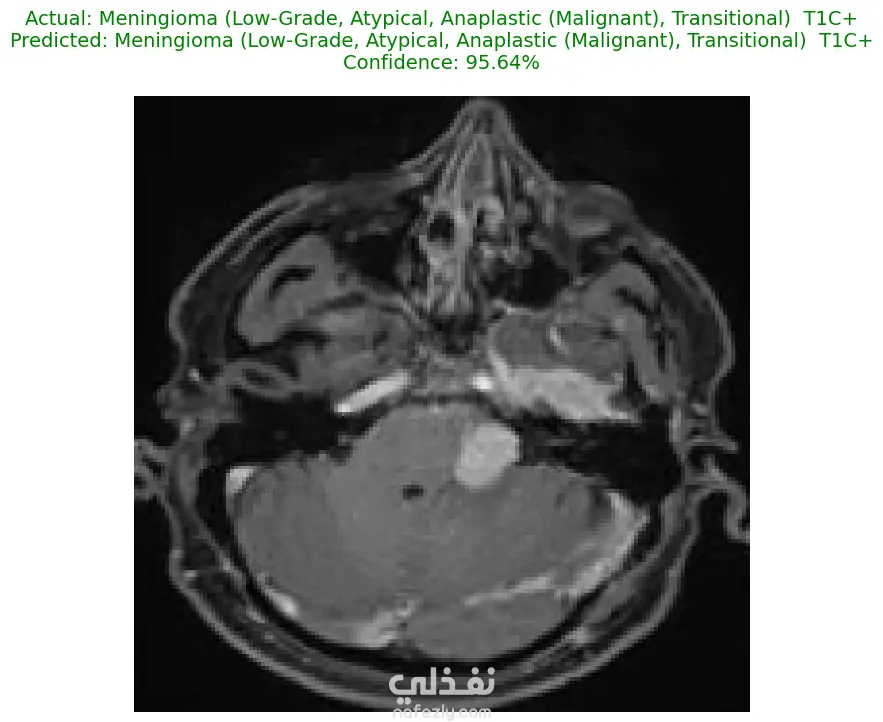

الوصف: قمت بتطوير نموذج تعلم عميق (CNN) قادر على التمييز بين 27 فئة مختلفة من الأورام والحالات الطبيعية بدقة تصل إلى 93%. شمل المشروع مراحل معالجة البيانات الضخمة، تنظيفها وموازنتها، وتصميم معمارية مخصصة لضمان الكفاءة العالية وتقليل استهلاك الذاكرة. المميزات التقنية: دقة استثنائية: حقق النموذج دقة تصل إلى 93% على بيانات التحقق (Validation Accuracy). معالجة البيانات الضخمة: تم العمل على قاعدة بيانات ضخمة، مع تطبيق استراتيجيات موازنة البيانات (Data Balancing) لضمان عدم انحياز الموديل. معمارية مخصصة: تم تصميم شبكة CNN تدعم تقنيات Batch Normalization لتسريع التعلم و Global Average Pooling لتقليل استهلاك الذاكرة وضمان استقرار النموذج. معالجة الصور: استخدام تقنيات OpenCV لقص الصور (Cropping) وإزالة الهوامش غير الضرورية لتركيز الموديل على منطقة الورم فقط. الأدوات والتقنيات المستخدمة: لغة البرمجة: Python. المكتبات الأساسية: TensorFlow / Keras. معالجة الصور: OpenCV & PIL. تحليل النتائج: Scikit-learn (Confusion Matrix & Classification Report). البيئة البرمجية: Google Colab (GPU Acceleration). النتائج المحققة: نموذج قادر على التعرف على أنواع نادرة من الأورام بدقة عالية. تقرير فني يوضح أداء الموديل لكل فئة (Precision & Recall). ملف نموذج جاهز للنشر (Deployment) بصيغة keras الحديثة. يمكنكم الاطلاع على الكود المصدري كاملاً والرسوم البيانية لتقييم أداء النموذج عبر رابط GitHub المرفق، كما يتوفر رابط تحميل النموذج المدرب داخل ملف الشرح.